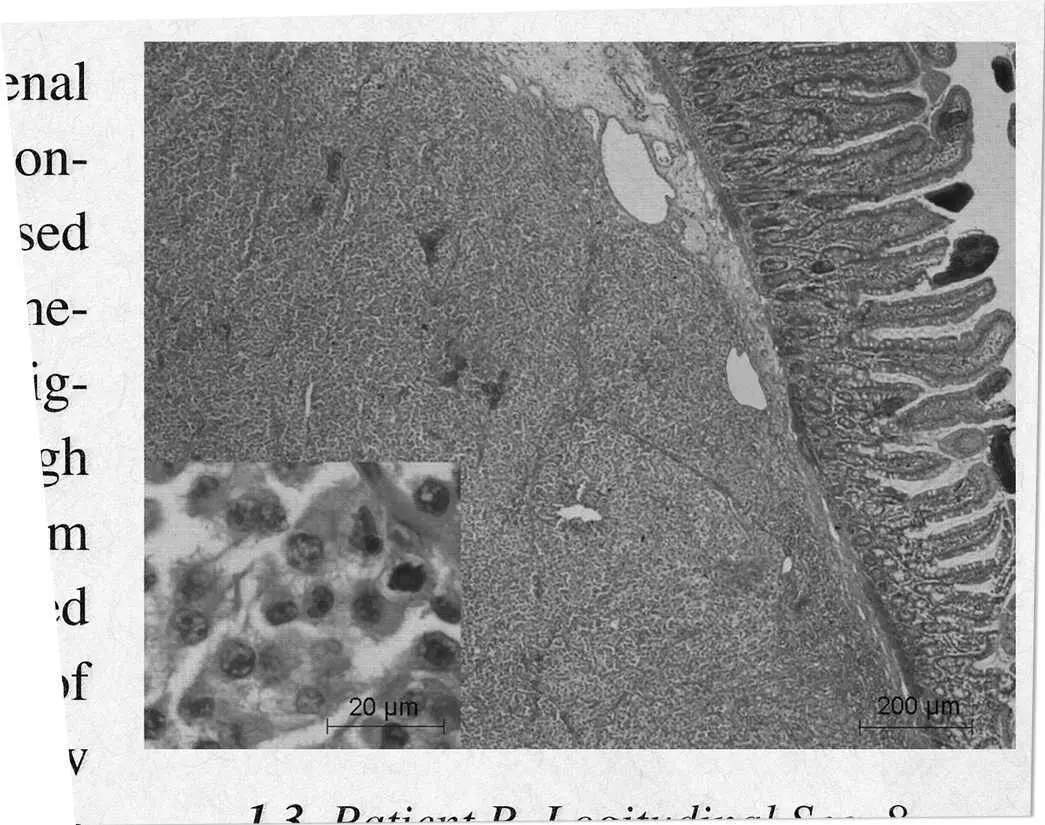

Fig. 1.2. Patient R, Longitudinal Section 8

From Fitzgerald, T., “On an Isolated Incidence of Non- Addison’s Hypoadrenal Uniform Hyperpigmentation in a Caucasian Male,” Journal of Investigative Dermatology 72: 351

Indeed, as far as she could tell, “On an Isolated Incidence of Non-Addison’s Hypoadrenal Uniform Hyperpigmentation in a Caucasian Male” was nothing more than a professional shrug of the shoulders. “The unusual uniform darkening in this individual can be linked to a marked increase in melanocyte-stimulating and adrenocorticotropic hormones, though all other pituitary and adrenal gland functions appear normal,” Dr. Fitzgerald wrote in his conclusion, hiding behind the oddly disembodied language of the medical professional. “No doubt further genetic studies need to be performed to ascertain the precise catalyst for the over-production of these hormones, which are not present in either parent or gene group. In all other areas, however, the patient is a normal, functioning male infant. Chance transmutation, it seems, has struck again” (354).